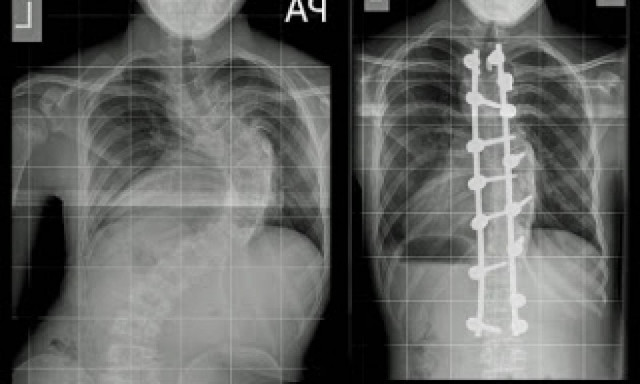

Ένας έφηβος, 14 ετών, ψηλώνει κατά περίπου δύο πόντους κάθε βράδυ, μετά από εγχείρηση επανόρθωσης της σπονδυλικής του στήλης.

Ο Harvey Legge, έπασχε εκ γενετής από σοβαρή σκολίωση η οποία μάλιστα απειλούσε την λειτουργία των ζωτικών του οργάνων.

Πρόσφατα λοιπόν υποβλήθηκε σε χειρουργείο σε εξειδικευμένη παιδιατρική κλινική όπου οι γιατροί σημείωσαν πως η κατάστασή του ήταν ιδιαίτερα σοβαρή γι' αυτό και έπρεπε να χειρουργηθεί.

Και ευτυχώς που έγινε καθώς το παιδί απαλλάχθηκε από την κλήση 90 μοιρών που έκανε το πάνω μέρος του σώματός του με αφόρητους πόνους ενώ συγχρόνως, κάθε βράδυ ψηλώνει κατά περίπου δύο εκατοστά.

Πλέον η κλήση της σπονδυλικής του στήλης έχει περιοριστεί στο 20% ενώ οι πόνοι έχουν υποχωρήσει αισθητά, με τον μικρό και τους γονείς του να δηλώνουν τρισευτυχισμένοι για τη συγκεκριμένη εξέλιξη.